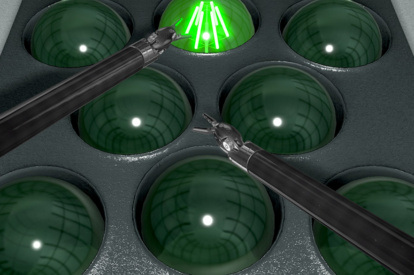

Robotic basic tasks modules allow the user to familiarize with and master the fundamental aspects of robotic skills, while clinical procedure modules let surgeons immerse themselves into partial or entire robotic virtual procedures.

Get a glimpse of the exercises included in the RobotiX Mentor, from the fundamental aspects of instrument manipulation to a variety of full procedures.

Robotic Basic Skills Module

Robotic Essential Skills Module

Fundamentals of Robotic Surgery Module